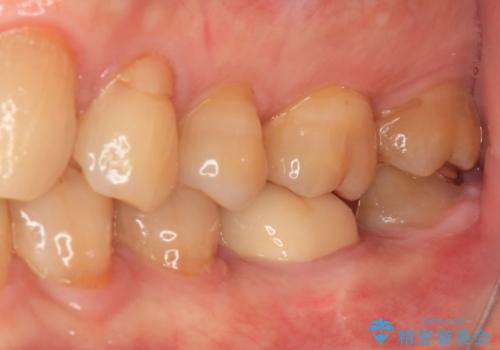

1番奥は歯肉に覆われている部分が大きいため、欠損部とむし歯の部分をゴールドインレーにて修復し、手前の歯はオールセラミッククラウンにて補綴治療を行うこととしました。

来院前から痛みはありませんでしたが、食事の度にものが挟まる不快感がありました。

処置後はスッキリとした環境になりました。